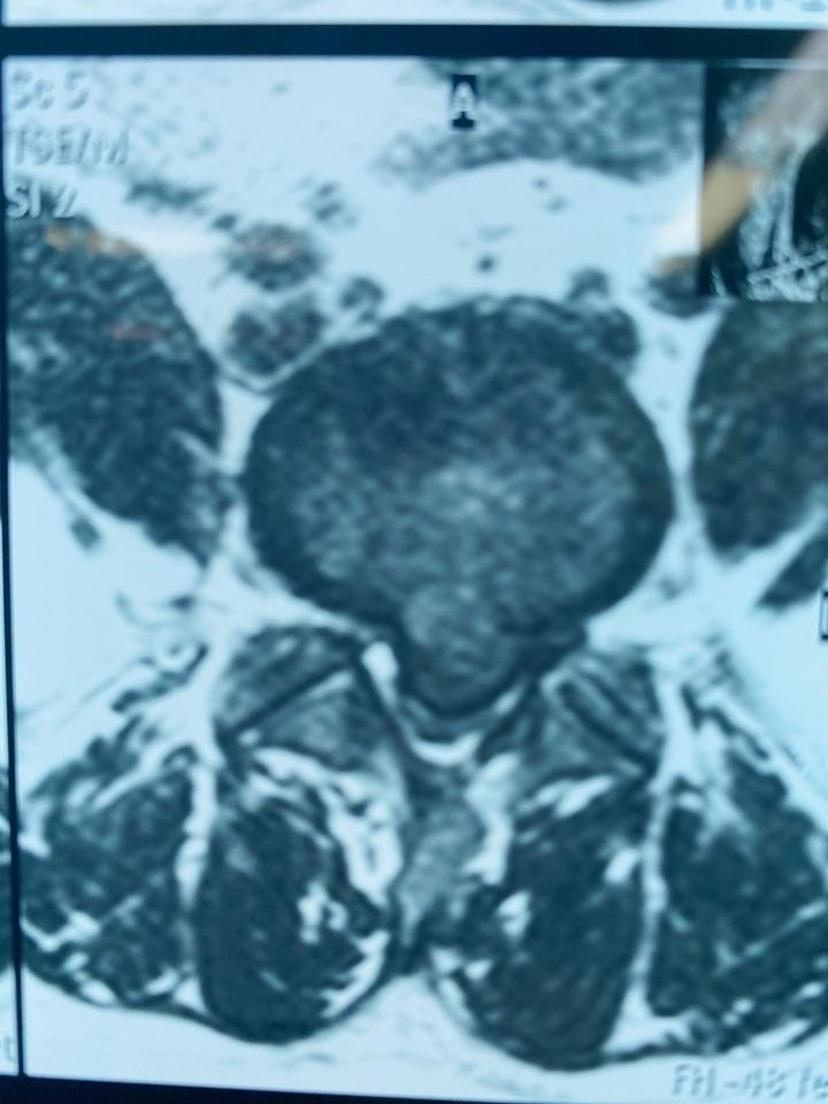

患者因腰痛诊断出腰5-骶1椎间盘突出5年了,这四天来腰背部疼痛难忍,双下肢麻木无力,会阴部麻木,不能站立、不能平躺,大小便排出困难,再次复查腰椎磁共振:腰5-骶1椎间盘全部脱出于椎管内导致椎管狭窄,双侧神经及硬膜囊完全受压,急诊采用双侧减压方式,取出串珠状游离的髓核组织,术后第三天恢复排便功能,大小便基本正常,症状解除,神经功能得到恢复!温馨提醒:(如果您患有腰椎间盘突出,突发腰痛及双下肢痛麻症状加重,出现会阴区麻木,性功能下降、大小便失禁或排出障碍,很可能就是椎间盘脱出导致的马尾综合症,建议尽快到正规医院脊柱外科就诊,防止不可逆的马尾神经损伤导致的严重后果)。腰5-骶1椎间盘脱出占满椎管全部空间,硬膜囊完全受压

磁共振平扫显示椎间盘脱出压迫硬膜囊